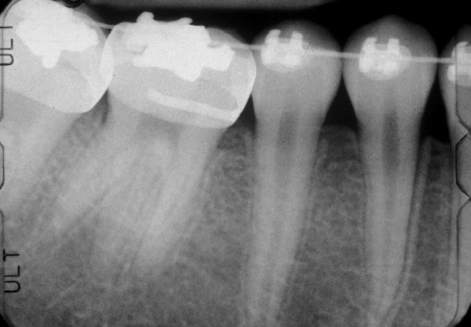

enlargement of the body and pulp chamber, most common in mand molars/ premolars, no tx necessary

taurodontism

enlarged pulp chamber -taurodontism

AD, AR, X-linked; both deciduous and permanent dentition are diffusely involved, affects enamel (soft, thin, easily damaged, susceptible to decay), dentin is exposed

amelogenesis imperfecta (AI)

hypoplastic (pitted), hypomaturation/ hypocalcification (snowcapped) AI with taurodontism